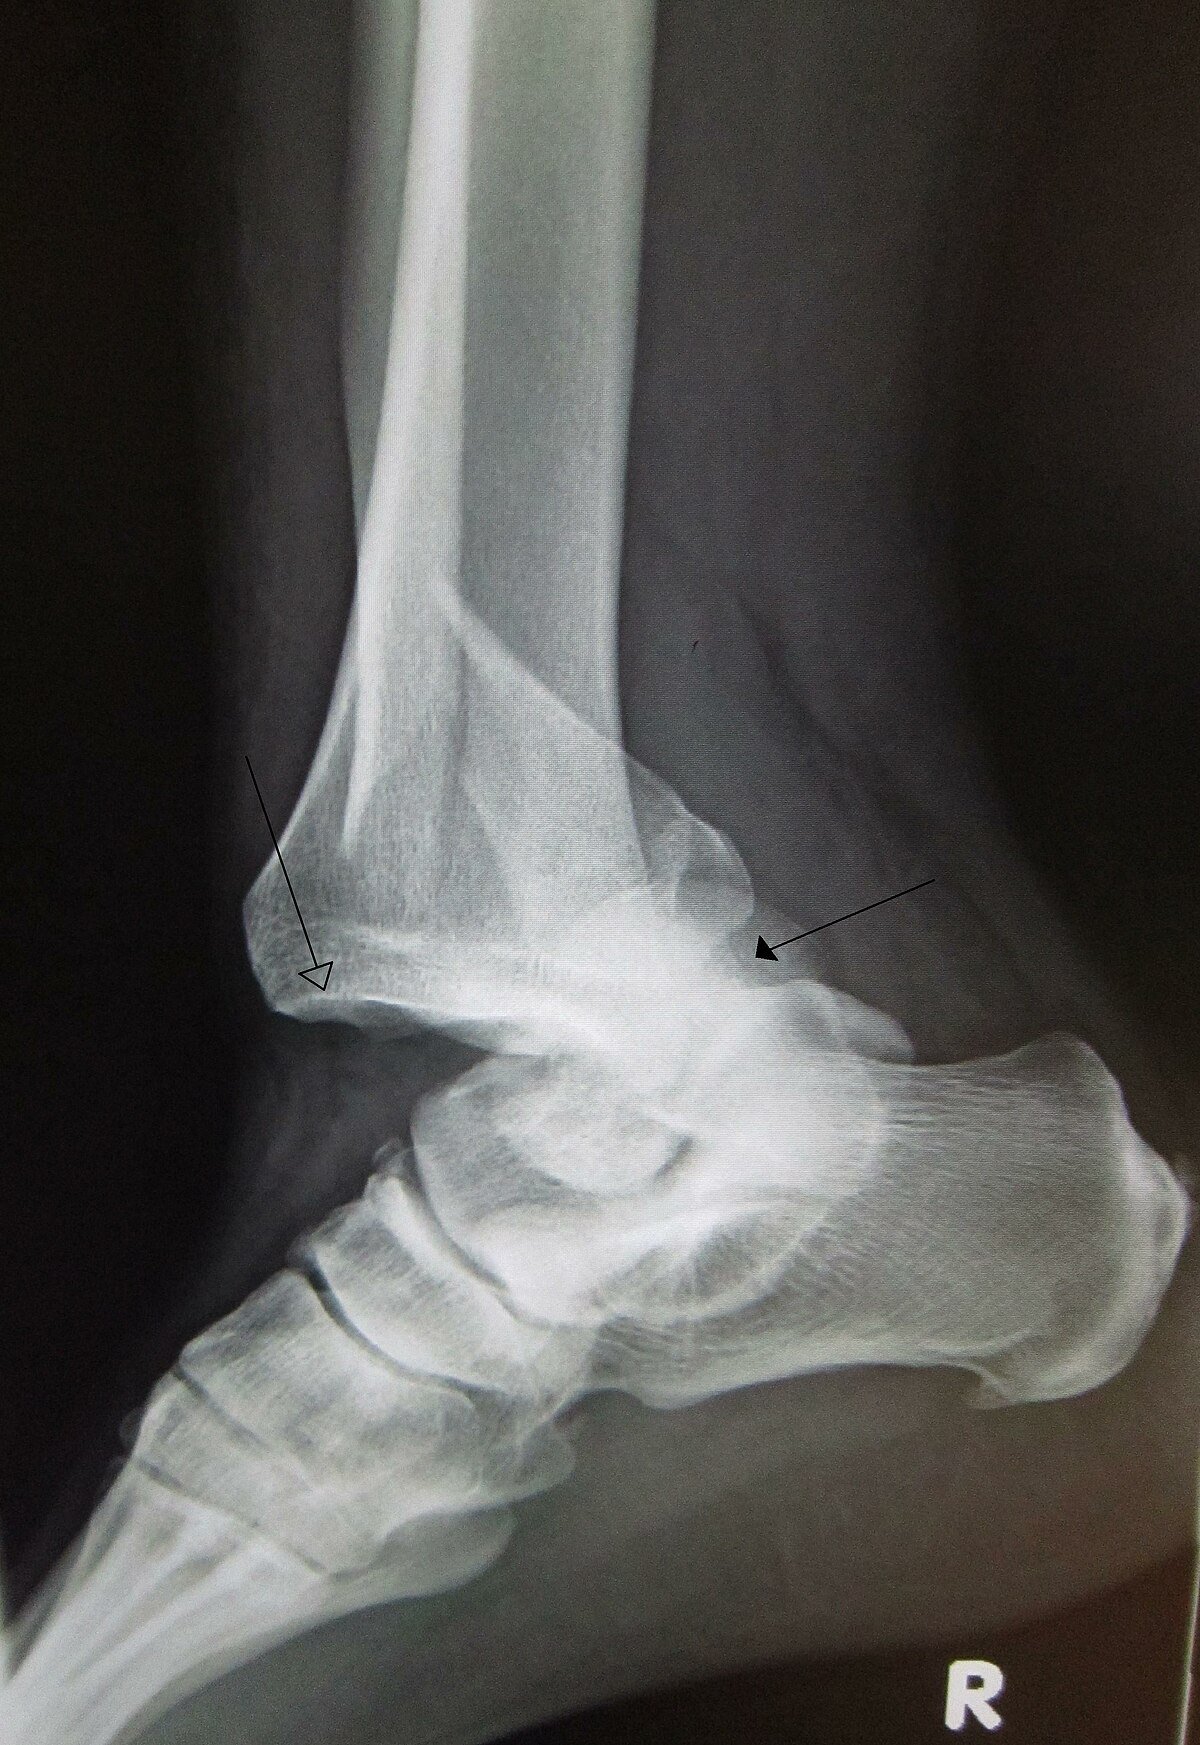

8. Check the X-ray of the injured limb after immobilization to see reposition of the bone in joint cavity

4. Fracture dislocation: here along with the dislocation a piece of neighbouring bone is avulsed from its position or totally broken depending upon the severity of injury.